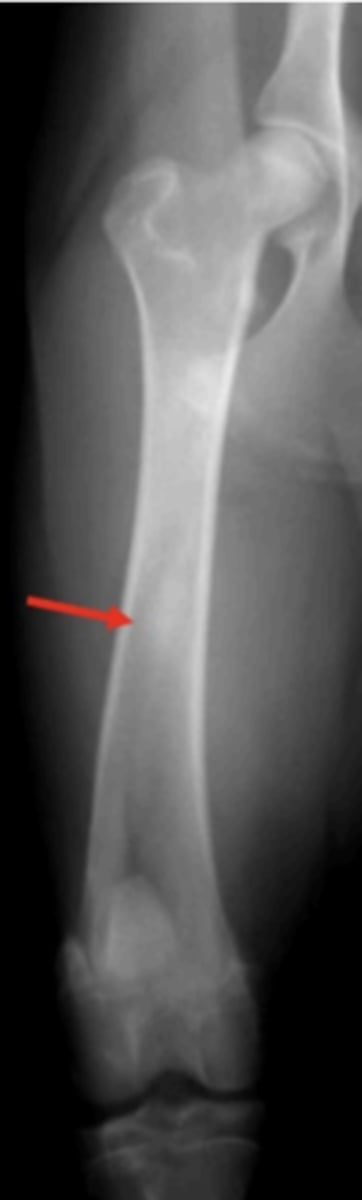

What fracture type is this?

Type IV

Which Salter-Harris fracture is pictured?